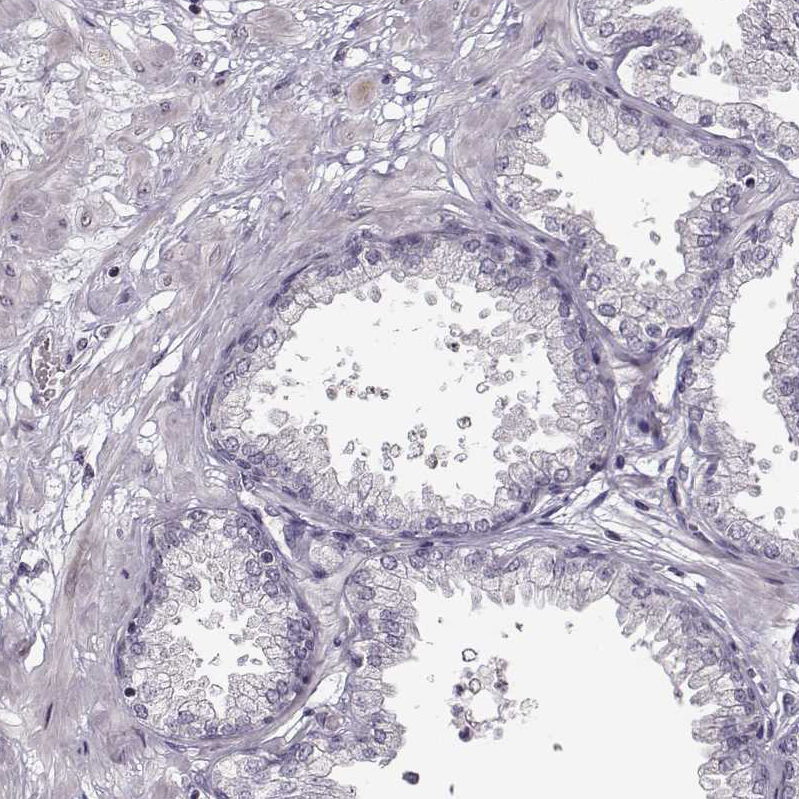

Immunohistochemical staining of human pituitary gland shows moderate to strong cytoplasmic positivity in glandular cells in anterior lobe.